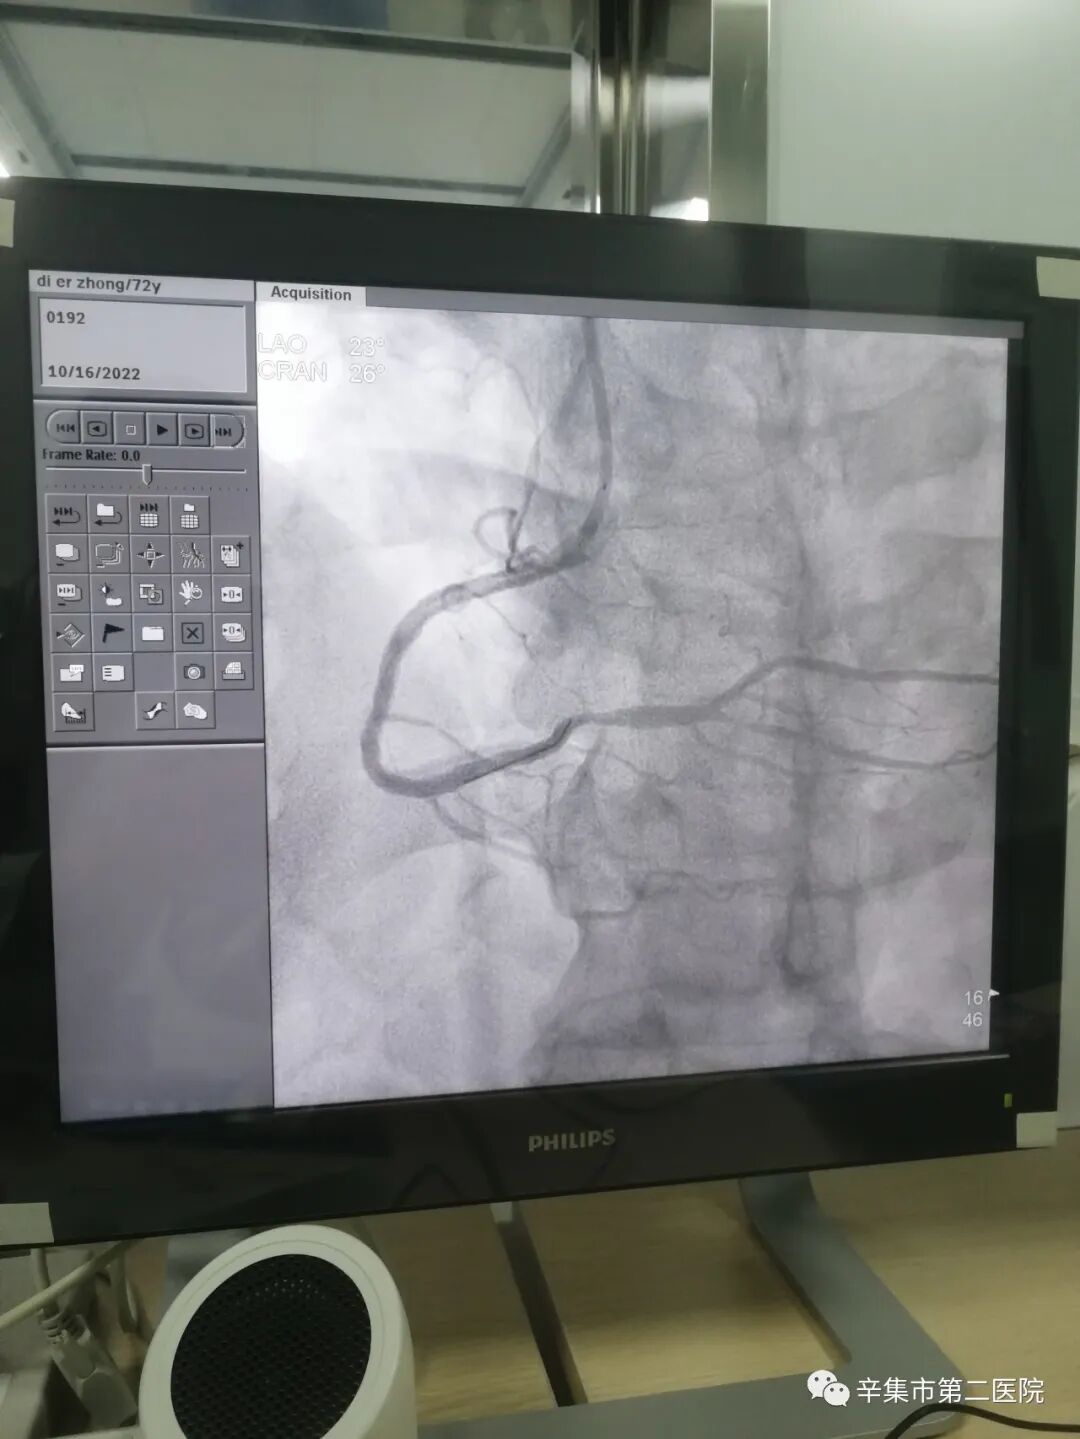

病历1冠脉造影术+经皮冠状动脉介入治疗(冠状动脉支架植入)

男性,72岁,发作性胸闷1月加重10天入院,入院后经积极药物治疗,患者仍有胸闷症状发作;

查冠脉造影示:右冠状动脉近段次全闭塞,

植入支架一枚;术后手术部位狭窄解除,无胸闷发作;